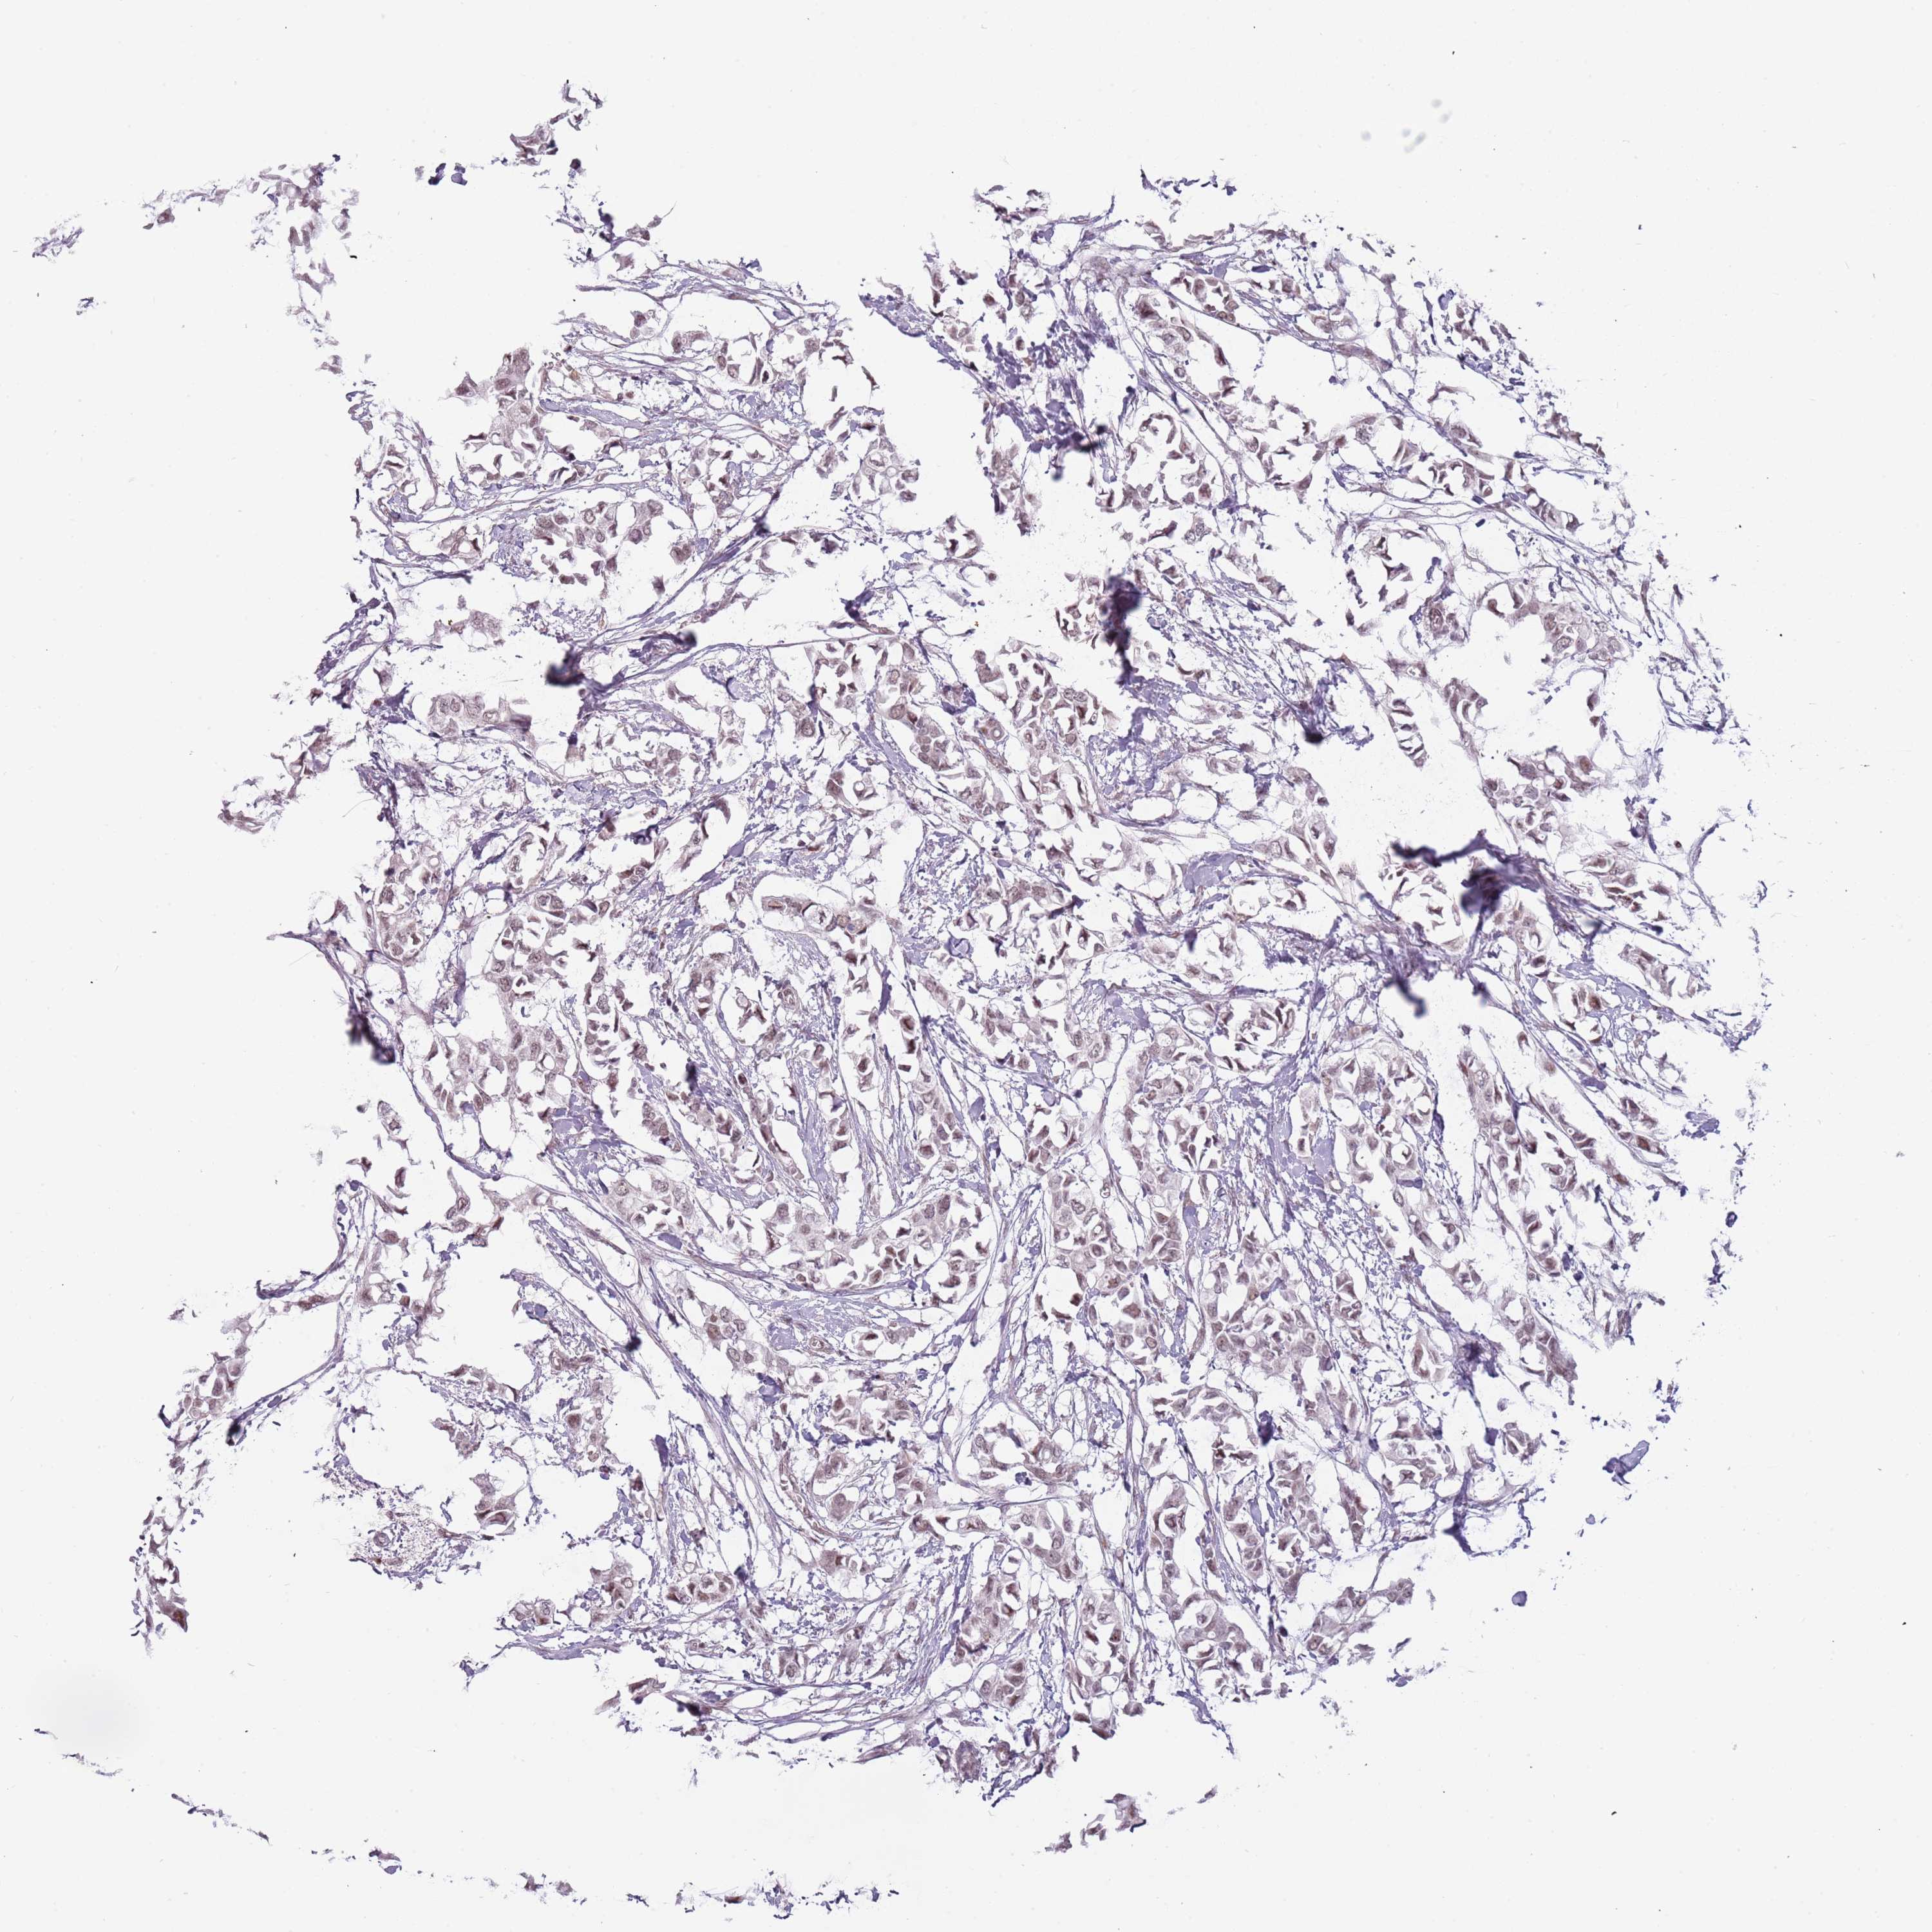

Breast cancer

Human cancer